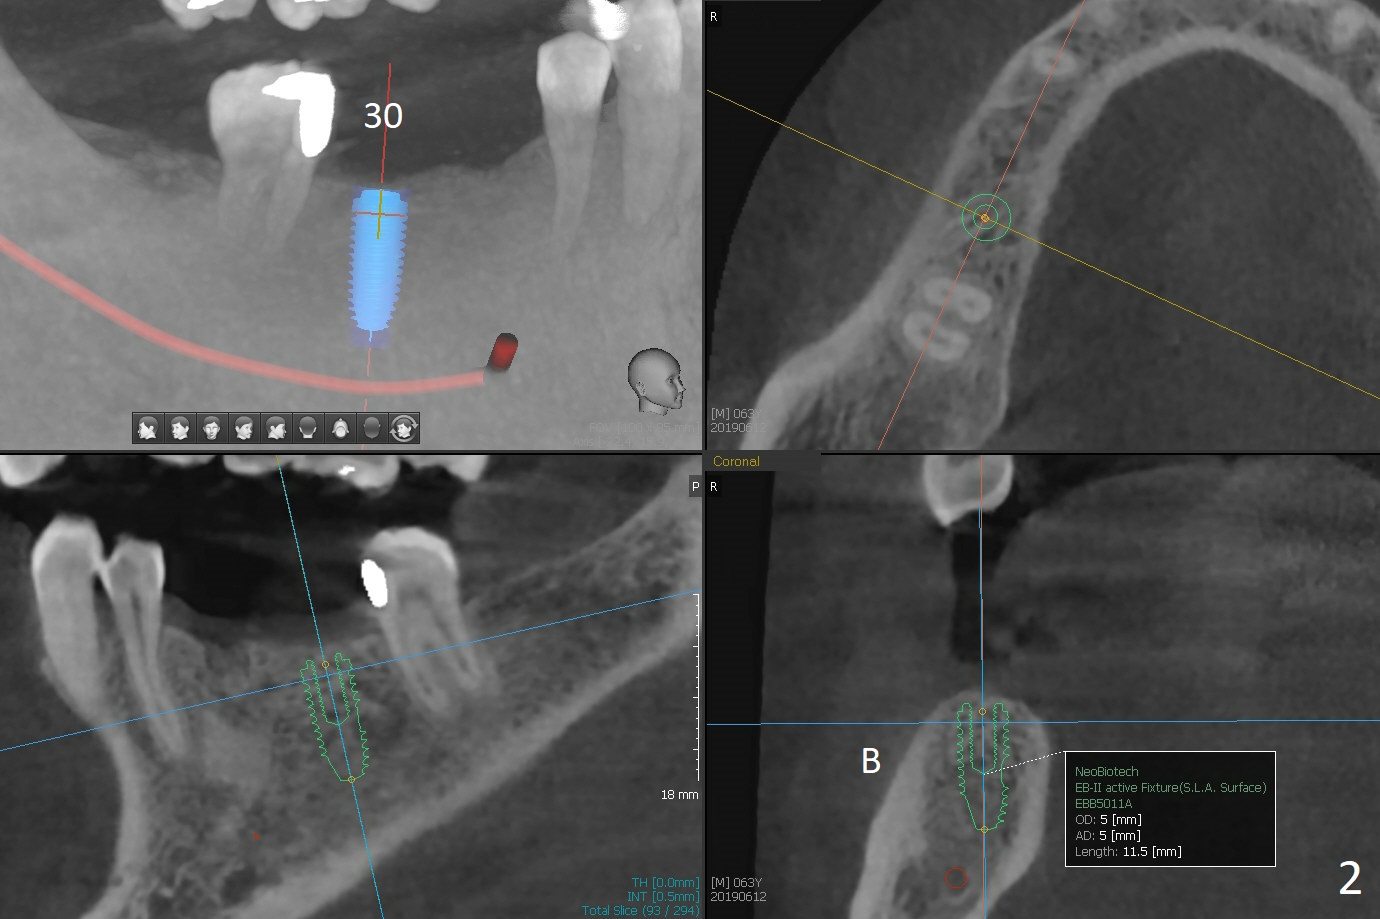

A 63-year-old man requests implants to replace a flipper at #29 and 30 (Fig.1). If torque is >25 Ncm for each implant (Fig.2,3 (2 mm bone buccolingually)), abutments will be placed immediately (using planning kit) for splinted provisional. Take photos for the flipper for a good bye party. Composite will be placed at #31 for MO leakage. Remove a small piece of residual root distal to #30 implant with curettage after osteotomy (Fig.4 <).